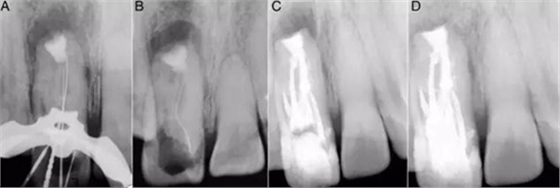

圖3:A:5個根管開口;B:DM根管傾斜走形,在MI頰側(cè);C和D:倒充填和MTA使用后的圖像。

接著,用K銼和手用擴孔銼進行根管預備,2%洗必泰、3%次氯酸鈉、生理鹽水交替沖洗并輔以超聲蕩洗。最后,MI備至80#K銼,近中根管備至F1,DM備至F4,遠中根管備至60#K銼,DI備至50#Nitiflex。根管內(nèi)封氫氧化鈣2周后行根尖手術(shù)。

復診在局部麻醉后翻開粘骨膜瓣,搔刮骨缺損,暴露根尖區(qū)。切除根尖2mm以消除根尖的薄弱邊緣。預備根尖5mm區(qū)域(3C),MTA倒充填(3D)。皮瓣復位后進行間斷縫合,5天后拆除縫線。